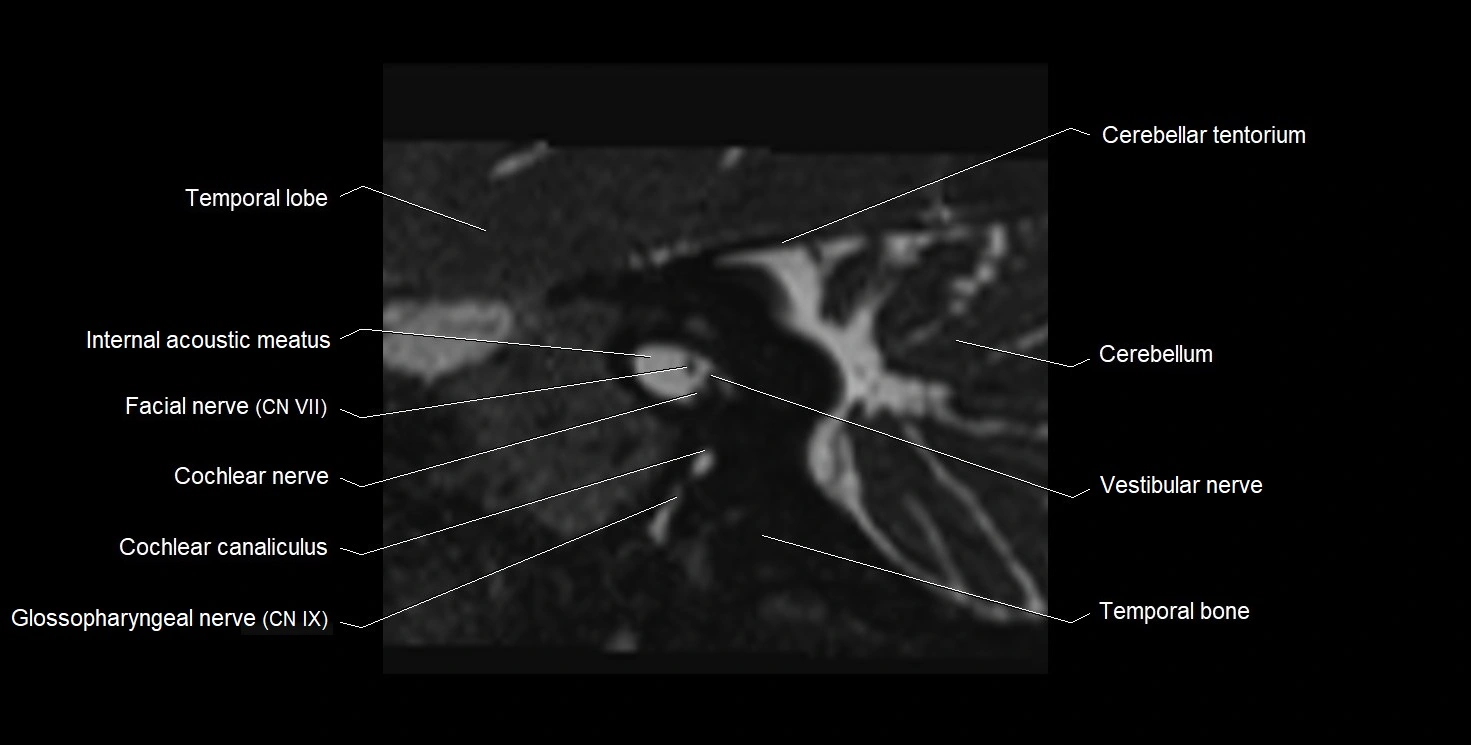

MRI Appearance

• The abducens nerve is a small, thin, linear structure

• Best visualized on high-resolution T2-weighted 3D MRI sequences (e.g., FIESTA or CISS)

• Seen as a hypointense (dark) line running from the brainstem at the pontomedullary junction, traversing the prepontine cistern, and entering Dorello’s canal under the petrosphenoidal ligament, then into the cavernous sinus, and finally the orbit

• May be challenging to visualize in standard MRI due to its small size

• Pathology may be inferred by absence, displacement, or enhancement of the nerve